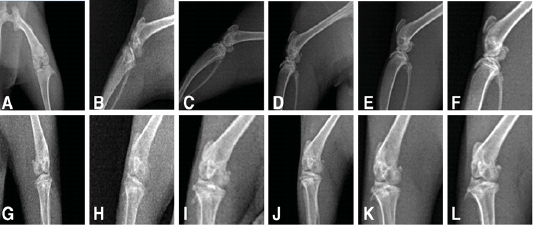

X-ray of the knee joints treated and untreated rats (A to F) showing lateromedial views, (G to L) anteroposterior views showing.